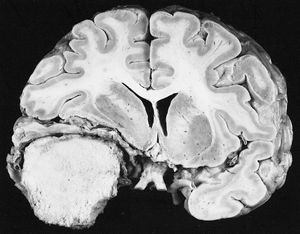

전 세계적으로 발생한 암의 약 18%는 감염과 관련이 있다.[93][144][9][60] 이 비율은 지역에 따라 다른데, 아프리카에서는 25%에 달하지만 선진국에서는 10% 미만이다.[93][9] 암을 유발하는 주요 감염원은 바이러스지만, 세균과 기생충도 암 발생에 기여할 수 있다. DNA 손상이나 유전체 불안정성을 일으키는 감염원이 암의 발병률을 높인다.종양바이러스라고 불리는, 바이러스 감염으로 인해 발생하는 대표적인 암으로는 간암과 자궁경부암이 있다.[145][61] 인유두종 바이러스(자궁경부암), 엡스타인-바 바이러스(림프증식성질환 및 비인두암), KSHV(카포시육종 및 원발삼출림프종), B형 간염 바이러스 및 C형 간염 바이러스(간세포암), 사람T세포림프친화바이러스 1형(T세포 급성림프구백혈병) 등이 이에 해당한다. 서구권에서 가장 흔한 종양바이러스는 인유두종 바이러스, B형 간염 바이러스, C형 간염 바이러스이다.[146][62] 미국에서는 인유두종 바이러스가 자궁경부암 외에도 질암, 외음부암, 음경암, 항문암, 직장암, 인후암, 설암, 편도선암 등을 유발한다.[147][63] 인유두종 바이러스의 E6 및 E7 암유전자는 세포 감염 시 종양억제유전자를 비활성화시키고, 세포의 유전자 불안정성을 높여 암 발병 가능성을 증가시킨다.[148][64] B형 간염 바이러스 감염자는 비감염자보다 간암 발병 가능성이 200배 높다.[149][65] 간경화증은 간염 바이러스나 과도한 알코올 섭취로 인해 발생하는데, 간경화증과 바이러스 감염이 동시에 발생하면 간암 발병 위험이 가장 높다.[149][65]

위나선균에 의해 발병하는 위암 등, 일부 기생충 감염도 발암 가능성을 높인다.[150][66] 위나선균이 위암을 유발하는 원리는 염증이나 세균의 독력인자로 인한 것으로 추정된다.[151][67] 암을 유발하는 주요 기생충으로는 빌하르츠 주혈흡충(방광암), 간흡충류, 타이간흡충, 간흡충(담관암)이 있으며, 기생충이 낳는 알로 인해 생기는 염증이 암을 유발하는 것으로 보인다.[152][68] 기생충 감염은 체내 발암물질을 증가시켜 암을 촉진하기도 한다.[153][69] 미코박테륨인 결핵균 감염으로 인해 생기는 결핵과 폐암 사이에도 관련성이 존재한다.[154][70]